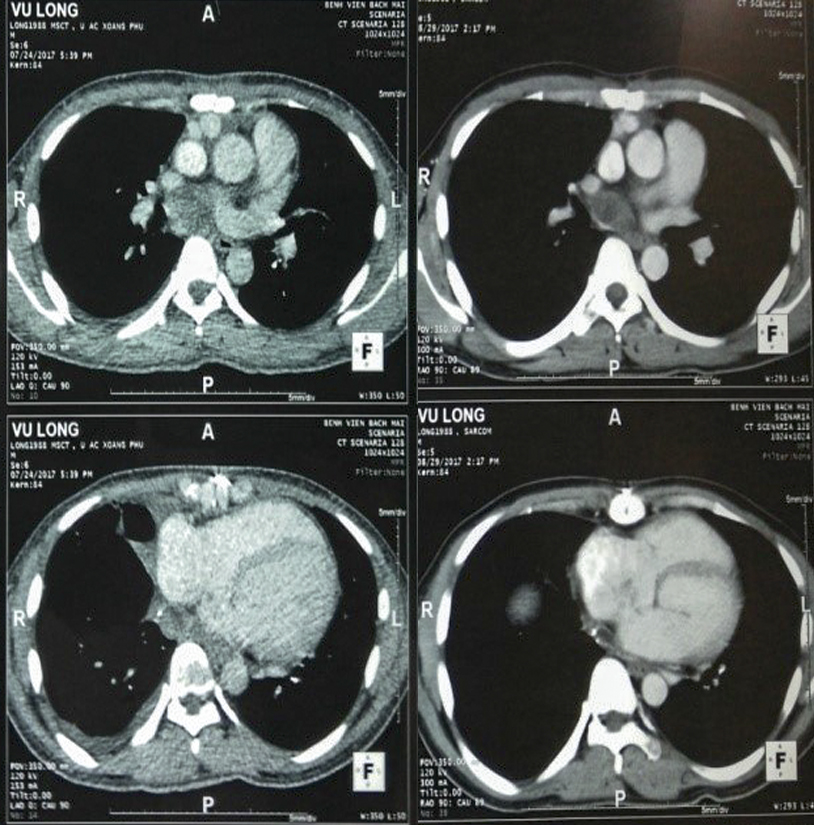

Hình 3: Hình ảnh chụp cắt lớp vi tính (CT) lồng ngực sau hai chu kỳ điều trị hoá chất

Bệnh nhân tiếp tục được điều trị theo phác đồ AIM thêm 2 chu kỳ. Bệnh nhân vẫn dung nạp tốt, không có hạ bạch cầu, công thức máu và chức năng gan thận trong giới hạn bình thường.